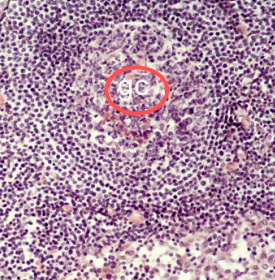

secondary lymphatic nodules in a lymph node

gc:

germinal

center in secondayr lymph node

contains

numerous

activated B

lymphocytes

red squares

mantle around germinal centers

red box is ____ in periphery of lymph node

subcapsular

sinus